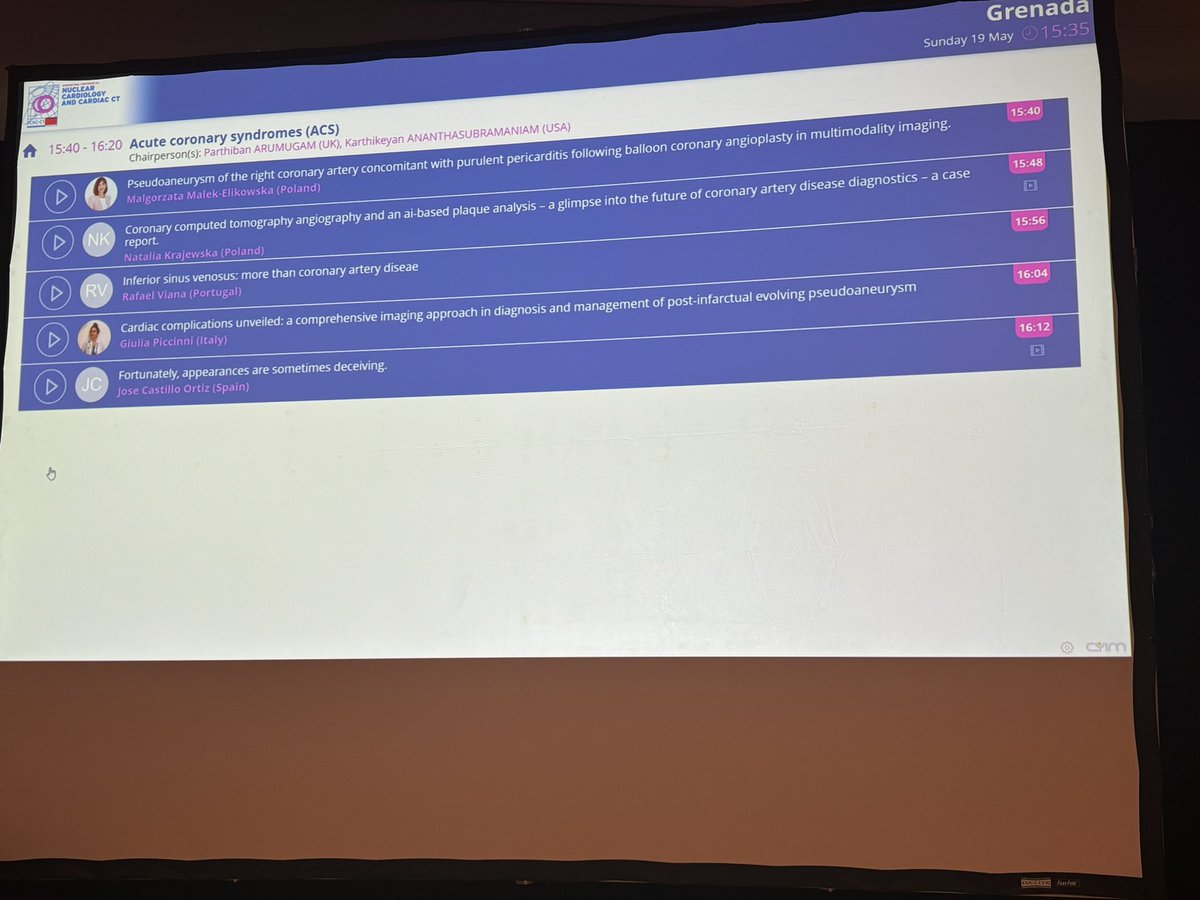

First day in #ICNCCT2024 meeting and honored to participate in the astonishing clinical case sessions after 2 years of the beggining of our CCTA program 👏👏👏Hospital Universitario Poniente